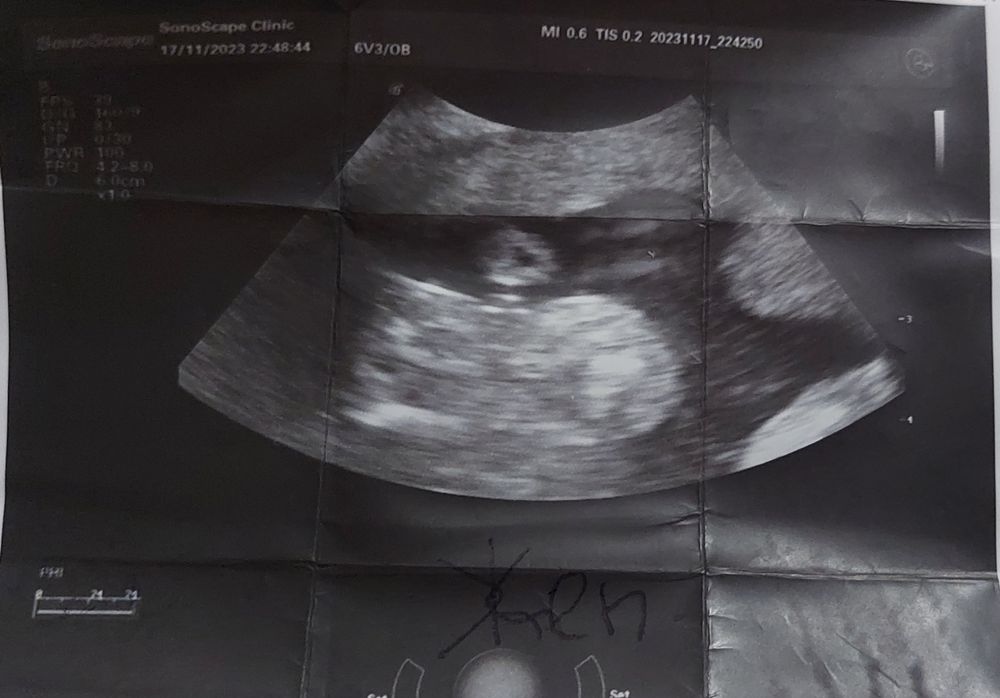

Сегодня узнаем кто в домике живет) (много фото узи) а вы как думаете?)

Плохое качество фото, видно что все они сняты между ног, но не чётко, вообще яичек нет вроде бы, значит девочка.

УЗИ 12 недель Точно девочка?)